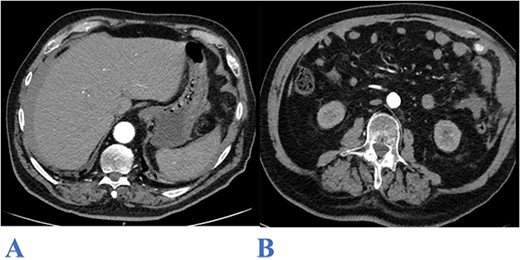

On arrival to emergency, the patient was haemodynamically unstable with a blood pressure of 75/25 mmHg, heart rate of 71 bpm, respiratory rate of 30/min, and was afebrile. His Glasgow Coma Scale fluctuated between 14 and 15. Initial examination showed a diffusely distended abdomen that was tense to palpation with peritonism localized to the LUQ. Laboratory investigations showed haemoglobin of 146 g/L, white cell and platelet counts of 10.4 × 103 and 171 × 103, respectively. An urgent computed tomography (CT) scan of the abdomen showed moderate to large volume haemoperitoneum in the right and left subphrenic spaces and along the anterior and left lateral abdominal walls, extending into the pelvis. There was active contrast extravasation to the left anterolateral abdomen at the position of the greater omentum (Fig. 1A, B). Whilst in emergency, the patient deteriorated further, requiring vasopressors for haemodynamic support with a repeat of full blood count showing haemoglobin of 114 g/L. A massive transfusion protocol was initiated and his anticoagulated state was reversed with an off-label use of Prothrombinex as per haematology team advice.

Axial CT abdomen image (arterial phase) showing: bilateral subphrenic hemoperitoneum (A) and contrast extravasation from the upper left lateral omentum (B).